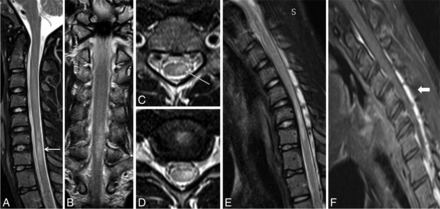

A 20-year-old male patient with weakness and wasting of the left hand muscles. Neutral position sagittal T2-weighted image (A) shows the normal appearance of the cervical cord. Axial T2-weighted flexion MR images (B and C) and postgadolinium T1 fat-suppressed images (D and E) show widening of the LDS with anterior displacement of the posterior dura and asymmetric cord atrophy, more on the left side, along with multiple flow voids within the posterior epidural space (arrow). Postgadolinium T1 fat-suppressed flexion MR sagittal image (F) shows an enhancing posterior epidural venous plexus extending from the C4 to T4 vertebral level (block arrow).

A 21-year-old man with asymmetric wasting of the bilateral hand muscles. Neutral MR T2-weighted sagittal and coronal (A and B) images show lower cervical cord atrophy with segmental hyperintensities in the cervical cord at the C6 and C7 vertebral levels (white arrow). Axial T2-weighted images (C and D) show asymmetric hyperintensities, more pronounced in the left half of the cervical cord (arrow). Flexion cervical MR STIR image (E) shows an enlarged posterior epidural space, which is seen as an enhancing posterior epidural venous plexus on the postgadolinium T1 fat-suppressed sagittal image (F) (block arrow).